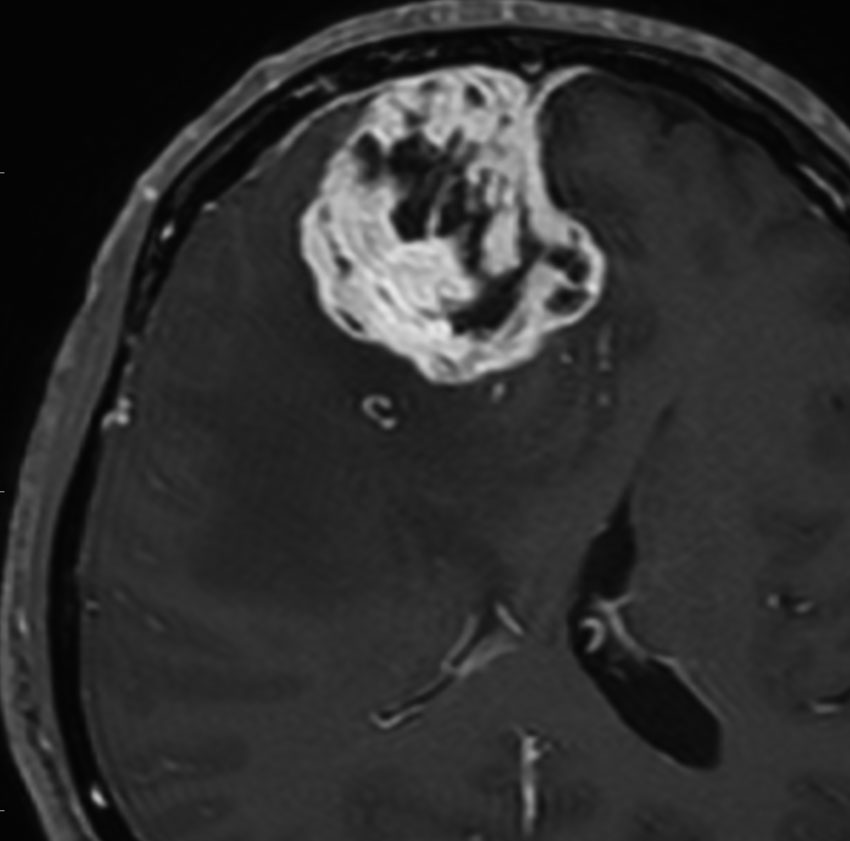

atypical meningioma WHO grade 2 非定型(異型性)髄膜腫

細胞密度が高く,若干の核異形成 anaplastyが見られます。MIB-1染色は15%でした。このような髄膜腫は手術誘発転移する能力を持っています。たとえば,右頭頂部傍矢状洞部の髄膜腫をソノペットなどの超音波破砕吸引装置を使って摘出すると,右前頭蓋底や右側頭部の離れた所に転移再発するという具合です。脳表転移とも硬膜下転移ともいえます。要するに手術で細胞をバラまくといろいろな所で根を張って成長する能力があるのです。